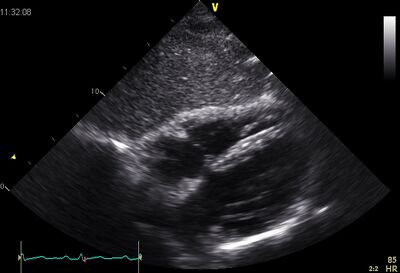

Echocardiographic views

Ap4ch.jpg Subcostaal4ch03.jpg

AP4CH Subcostal